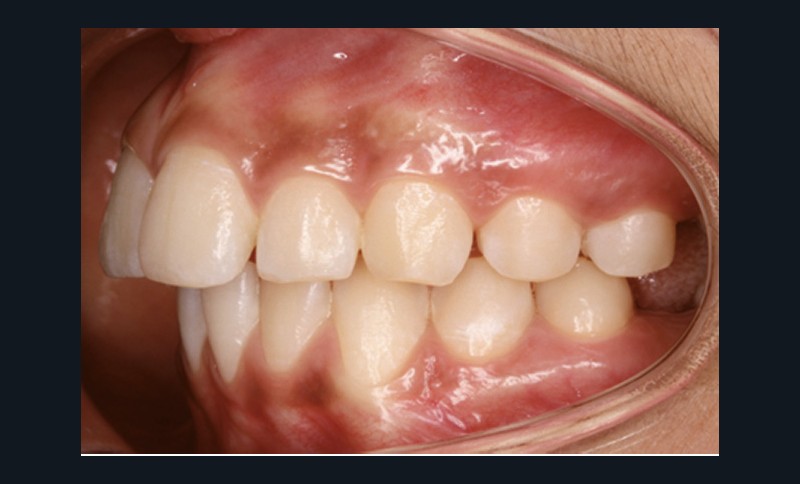

Examen endobuccal (fig. 2a-e)

L’hygiène est satisfaisante et le parodonte sain. On note aux deux arcades l’absence des premières molaires et la fermeture partielle des espaces d’extraction avec mésiorotation marquée de 17, 27 et 37. À la mandibule, l’encombrement antérieur est estimé à 2 mm et les espaces d’extraction résiduels à 12 mm.

Dans le sens transversal, malgré une occlusion correcte des secteurs latéraux, on observe une endoalvéolie maxillaire et une non-concordance des médianes incisives avec déviation de la médiane mandibulaire vers la droite. Le recouvrement incisif est normal.